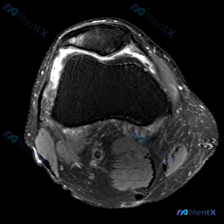

看到一份膝关节轴位MRI的读片资料,软骨异常是核心发现,整理了影像特征和完整分析思路,和大家分享讨论。 一、影像基本信息 这是膝关节髌股关节层面的脂肪抑制序列MRI(PD-FS或T2-FS),图像特征: 1. 髌骨、股骨皮质低信号,骨髓脂肪信号正常 2. 核心异常:髌骨后方关节软骨信号不均匀,局部高...

刚看到这份膝关节轴位MRI的分析资料,整理一下思路,这个病例其实挺容易踩坑的,分享给大家一起讨论。 病例影像核心信息 本次提供的是膝关节轴位MRI(T2WI/质子密度脂肪抑制序列),核心发现如下: 1. 髌股关节:髌骨软骨面全层高信号改变,股骨滑车中央及内侧软骨也可见广泛高信号;髌股关节间隙可见明显...

刚看到一例膝关节MRI读片的病例,整理了完整的影像发现和分析思路分享给大家,这个病例其实挺容易踩坑的。 病例影像资料 这是膝关节MRI T2序列轴位图像,读片结果整理如下: 1. 髌股关节: 髌骨后方关节软骨不连续,信号增高、形态毛糙,可见片状高信号,提示软骨损伤磨损;股骨滑车关节面软骨同样信号增高...